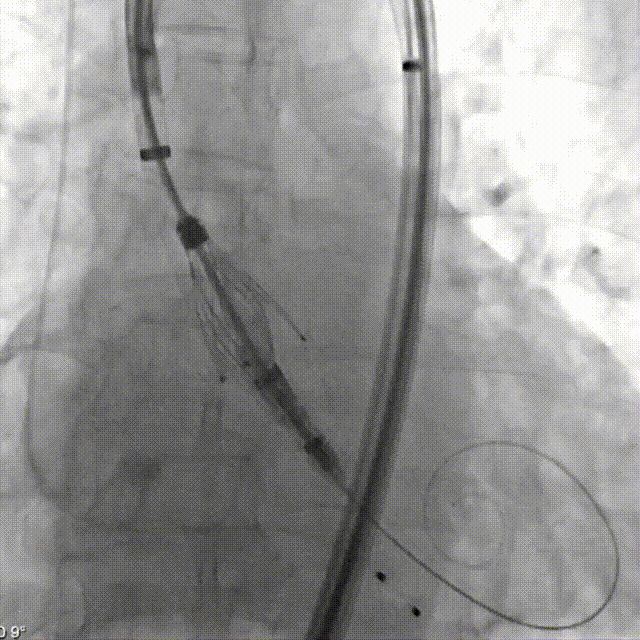

术中影像

冠脉造影

导引鞘定位STJ

定位键展开

瓣膜同轴调整